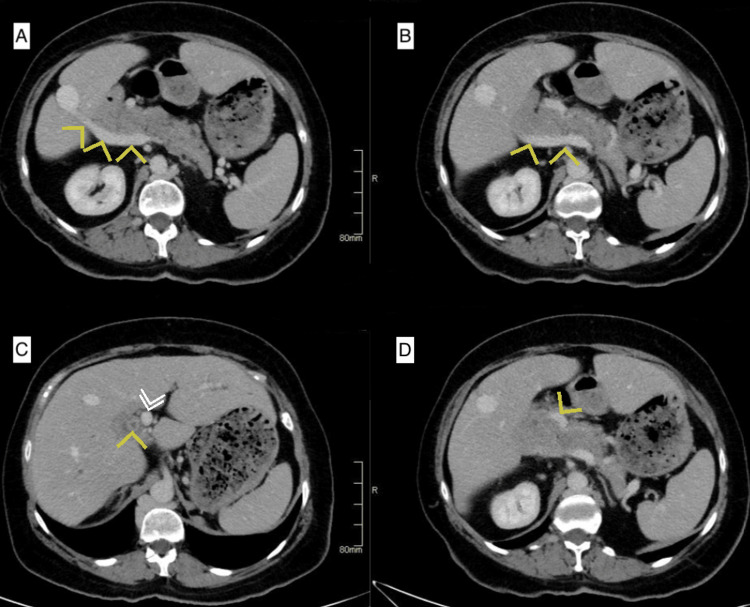

A 60-year-old female, with a history of laparoscopic cholecystectomy in 1996, which was converted to an open approach due to bleeding from an unidentified vessel, was referred to our practice for surgical management of a common bile duct stone that was not amenable to endoscopic retrograde cholangiopancreatography (ERCP). An abdominal computed tomography (CT) scan was obtained at our facilities to better delineate the patient’s biliary anatomy. The CT scan revealed multiple incidental findings of intestinal malrotation, a left-sided inferior vena cava (IVC), azygous continuation of the IVC, and a double portal system, characterized by the presence of two distinct portal veins entering the liver. In this scan, the superior mesenteric vein was seen giving a branch anterior to the pancreas before joining the splenic vein behind the pancreas (Figure 1).

This anterior branch continues towards the porta hepatis as a portal vein, and the posterior branch joined by the splenic vein continues laterally to the right and enters the liver at its edge close to segment VI as the second portal vein (Figure 2). The two portal veins were noted to communicate inside the liver parenchyma near segment VIII (Figure 3).